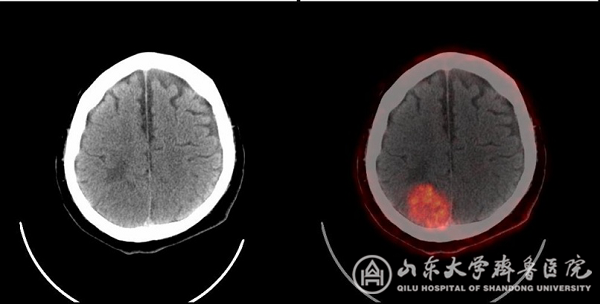

图4 CT未能清晰显示右侧顶叶病灶,而PET/CT示明显前列腺癌脑转移